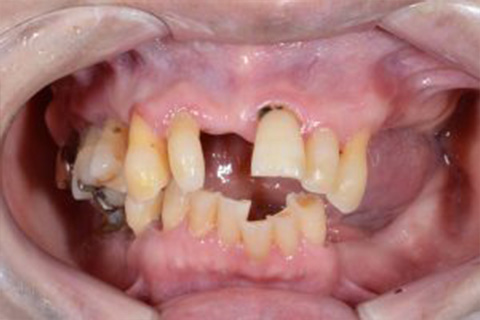

症例1

歯がグラグラで噛めない。自然な入れ歯で綺麗にしたい。という主訴でご来院頂いた患者様に対して特殊プラスチックを使用した総入れ歯(入れ歯)とコーヌスクローネ義歯(入れ歯)の症例

術前

入れ歯での治療後

最後にこのページの一番初めにのっていた方の治療前の写真をのせておきます。治療前とは比べものにならないぐらい自然な入れ歯が入っていることがお分かりになられると思います。

トップの写真の治療前の状態